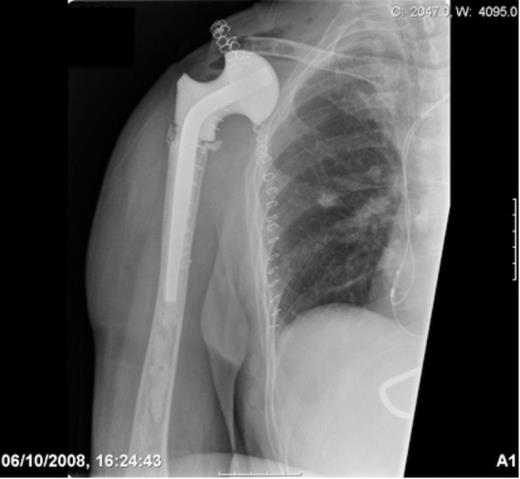

Post-operative radiograph demonstrating reconstruction using a hip spacer following extra-articular scapula resection

During the pre-operative consent process the patient stated if it was found that limb salvage was not technically possible intra-operatively, she did not wish to have a forequater amputation conducted and would rather the tumour be left untreated due to cosmetic concerns. A Tickhoff-Linberg procedure of the right shoulder was subsequently conducted with en-bloc resection of the scapula, distal clavicle and proximal humerus. In order to reconstruct the shoulder girdle, a hip spacer (spacer G by Orthodynamics) was cemented into the proximal humerus with the soft tissues tensioned appropriately. A synthetic mesh (LARS ligament by Corin) was then sutured over the prosthesis and secured to the osteotomised clavicular remnant and chest wall with non-absorbable sutures.

The patient made an uneventful post-operative recovery. The histopathological report confirmed a high-grade spindle cell sarcoma that had been completely excised with 2mm margins. Her wounds healed well with no complications and she retained very good hand, elbow and wrist function but no active motion of her shoulder.